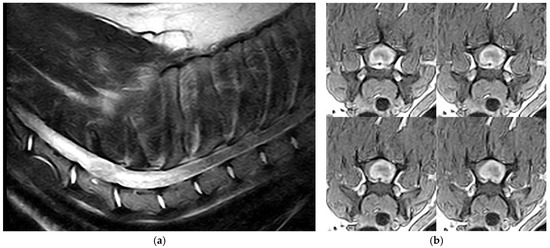

Canine Hemangioblastoma: Case Series and Literature Review

by Çağla Aytaş, Alberto Cauduro, Cristian Falzone, Stefania Gianni, Anna Tomba and Carlo Cantile

Human hemangioblastoma is a benign, slow-growing, highly vascular neoplasm. The tumor most commonly arises in the cerebral hemispheres and cerebellum, where it is more frequently observed in patients with von Hippel–Lindau disease. In veterinary medicine, hemangioblastoma has only been described in the central [...] Read more.

Human hemangioblastoma is a benign, slow-growing, highly vascular neoplasm. The tumor most commonly arises in the cerebral hemispheres and cerebellum, where it is more frequently observed in patients with von Hippel–Lindau disease. In veterinary medicine, hemangioblastoma has only been described in the central nervous system of dogs and in the skin of lambs. Our study aimed to characterize the clinical and neuropathological features of five cases of canine spinal cord hemangioblastoma and one case of sciatic nerve localization, and to compare these results with those reported in the veterinary literature. Diagnoses were achieved by neurological examination, neuroimaging, surgery or post-mortem examination, histopathology, and immunohistochemistry. All tumors were composed of numerous, haphazardly arranged capillaries lined by plump endothelium and interstitial fusiform to stellate stromal cells. Immunohistochemically, the stromal cells were strongly immunolabeled with NSE and carbonic anhydrase IX and were negative for von Willebrand factor VIII and inhibin-α. Canine hemangioblastoma exhibits morphological and immunohistochemical features comparable to the human counterpart, although the latter is mostly positive for inhibin-α. Surgery may be effective in cases of intradural-extramedullary and peripheral nerve locations, as in humans. This is the first report of peripheral nerve hemangioblastoma in animals. Full article

(This article belongs to the Section Veterinary Clinical Studies)

Show Figures

Figure 1